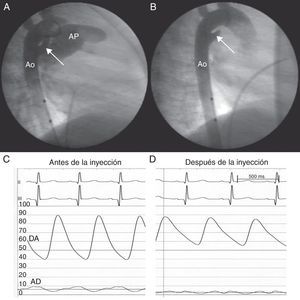

Anteriormente a cualquier intento de cruzar este ductus, se realizó una angiografía en aorta (Ao) descendente con catéter pigtail, que demostró un gran ductus (fig. A). Inmediatamente después se observó un aumento de presión diastólica (fig. C y D). Una segunda angiografía demostró oclusión completa del ductus (fig. B).

Pasados 60 min de monitorización continua, se observó disminución progresiva de la presión diastólica. Una nueva angiografía demostró repermeabilización del ductus. Se procedió al cierre mediante implantación de dispositivo Amplatzer® Duct Occluder II (AGA Medical Corp.; Plymouth, Minnesota, Estados Unidos) con base en medidas tomadas en la primera angiografía. El seguimiento extrahospitalario ha confirmado estabilidad del dispositivo y ausencia de flujo residual.

El cierre funcional intermitente del conducto arterioso está típicamente asociado a la manipulación de catéteres. En nuestros casos, el espasmo ocurrió después de la angiografía. En ambos pacientes, la monitorización continua de presión arterial nos permitió diagnosticar el espasmo y la posterior repermeabilización del ductus. Creemos que no se debería subestimar la variabilidad de tamaño de los ductus grandes. Mediante la vigilancia de presión diastólica, se podría evitar errores de medida y, por lo tanto, la embolización de los dispositivos de cierre de los conductos arteriosos.